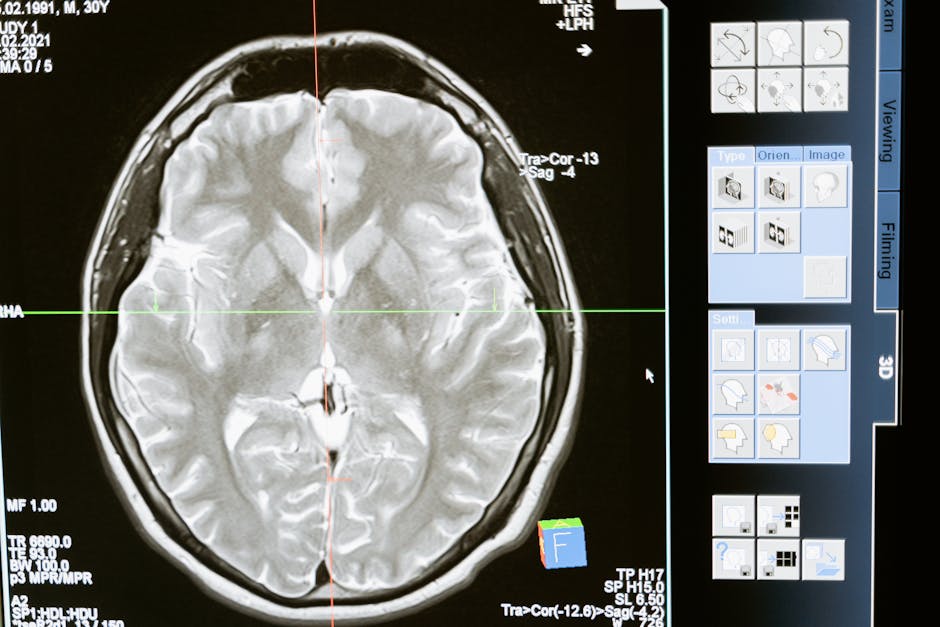

A striking fact has emerged in the field of dementia research: symptoms of early dementia can be reversed through bespoke treatment plans tailored to the individual’s specific needs. This groundbreaking finding has significant implications for the millions of people worldwide affected by cognitive decline. A recent study demonstrated that by addressing personal nutritional deficiencies, ongoing infections, and environmental exposures, patients with early-stage dementia experienced notable improvements in their symptoms. This personalized approach challenges the conventional view that dementia is an irreversible condition, offering new hope for those affected and their families.

The complexity of dementia as a condition is multifaceted, involving a combination of genetic, environmental, and lifestyle factors. As the global population ages, the incidence of dementia is expected to rise, making it one of the most significant health challenges of the 21st century. Despite extensive research, the causes of dementia remain not fully understood, and current treatments primarily focus on managing symptoms rather than addressing the underlying causes. The emergence of bespoke treatment plans as a potential solution marks a pivotal shift in how dementia is approached, emphasizing the importance of personalized medicine in improving patient outcomes.

Analysis of the outcomes from these bespoke treatment plans reveals a significant improvement in cognitive function among patients with early dementia. The data suggest that by addressing the root causes of cognitive decline, it is possible to not only halt the progression of dementia but also to reverse some of the symptoms. This finding has profound implications for our understanding of dementia and how it should be treated. It underscores the need for a more holistic and personalized approach to healthcare, one that takes into account the intricate interplay between genetic, environmental, and lifestyle factors. Furthermore, it highlights the importance of early intervention, as the effectiveness of these plans is greatest when implemented in the early stages of cognitive decline.